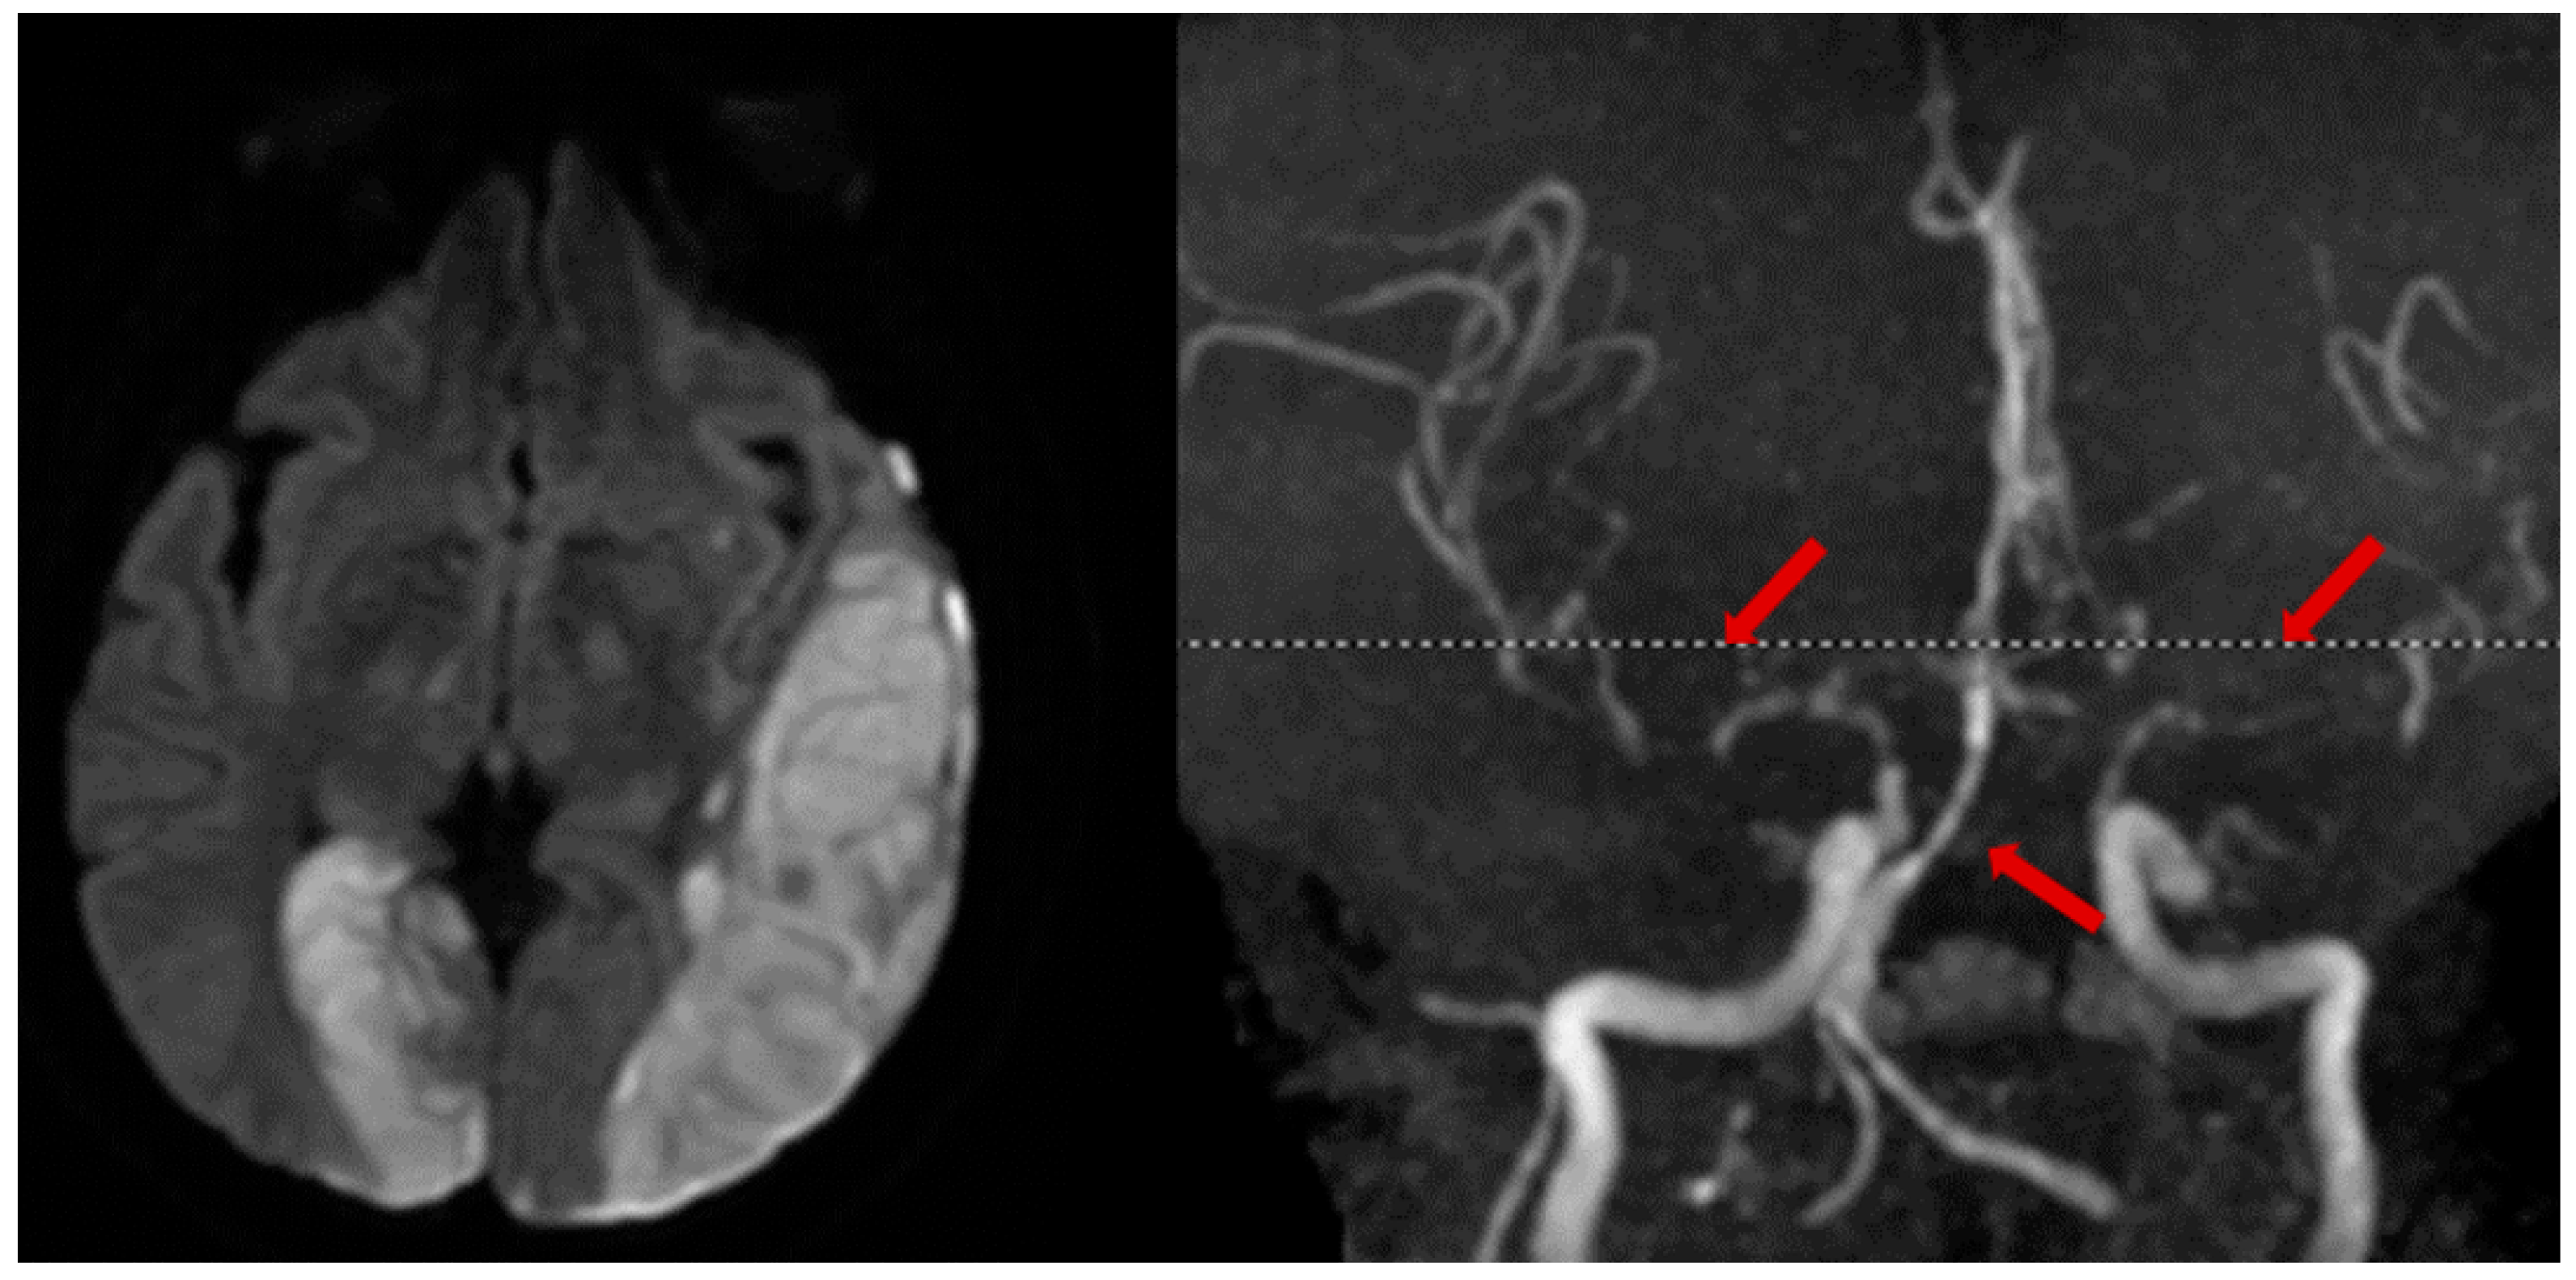

2.3. Cervical Artery Dissection

- Debette, S.; Leys, D. Cervical-artery dissections: Predisposing factors, diagnosis, and outcome. Lancet Neurol. 2009, 8, 668–678. [Google Scholar] [CrossRef] [PubMed]

- Kraus, R.R.; Bergstein, J.M.; DeBord, J.R. Diagnosis, treatment, and outcome of blunt carotid arterial injuries. Am. J. Surg. 1999, 178, 190–193. [Google Scholar] [CrossRef]

- Singh, R.R.; Barry, M.C.; Ireland, A.; Bouchier Hayes, D. Current diagnosis and management of blunt internal carotid artery injury. Eur. J. Vasc. Endovasc. Surg. 2004, 27, 577–584. [Google Scholar] [CrossRef]

- Baumgartner, R.W.; Arnold, M.; Baumgartner, I.; Mosso, M.; Gönner, F.; Studer, A.; Schroth, G.; Schuknecht, B.; Sturzenegger, M. Carotid dissection with and without ischemic events: Local symptoms and cerebral artery findings. Neurology 2001, 57, 827–832. [Google Scholar] [CrossRef]

- Morel, A.; Naggar, O.; Touzé, E.; Raymond, J.; Mas, J.; Meder, J.; Oppenheim, C. Mechanism of ischemic infarct in spontaneous cervical artery dissection. Stroke 2012, 43, 1354–1361. [Google Scholar] [CrossRef]